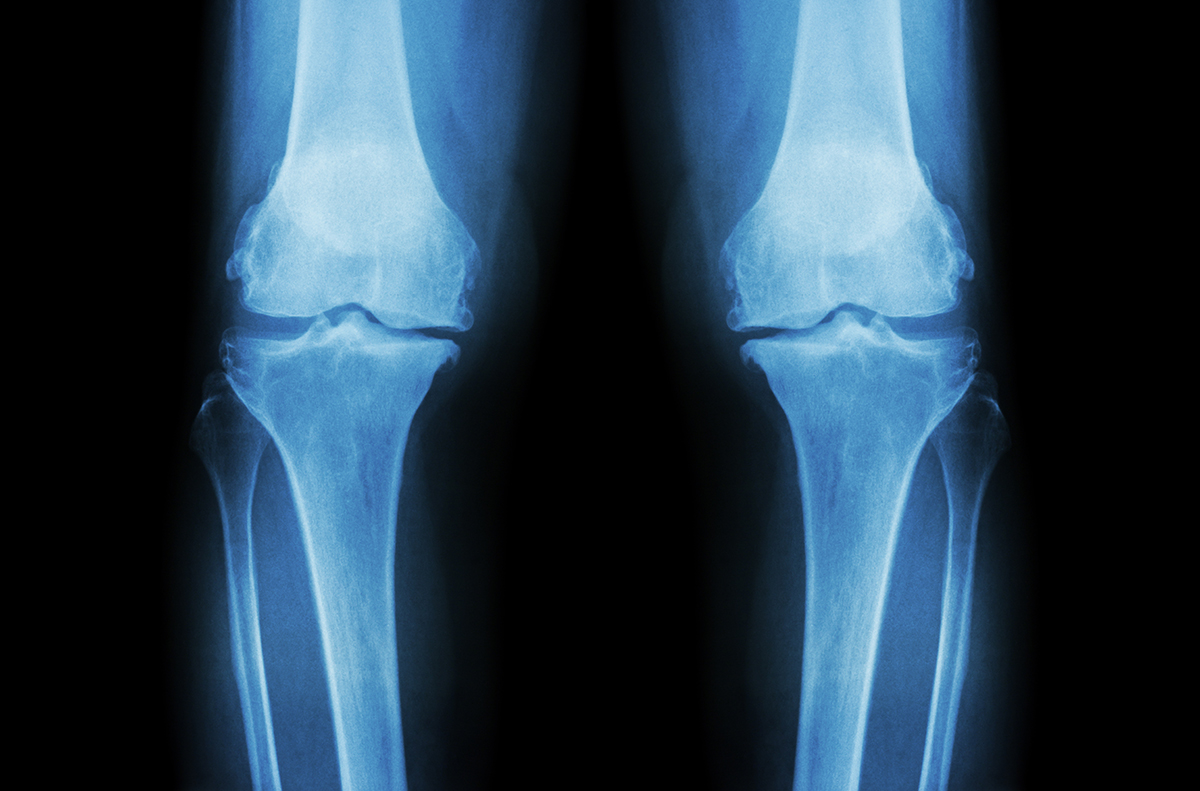

软骨的功能是吸收震动,减少摩擦,支撑关节和骨骼。正如你所想象的,跑步、散步等重复性运动会导致软骨损伤和退化。随着时间的推移,身体产生修复软骨所需胶原蛋白的能力下降,这一问题会更加严重。

由此导致的两种主要疾病是骨关节炎和类风湿关节炎。在小规模研究中,患者服用II型胶原蛋白后疼痛减轻,关节功能和活动性更好。这表明,加入软骨所需的营养素,可以抵消这种退化。